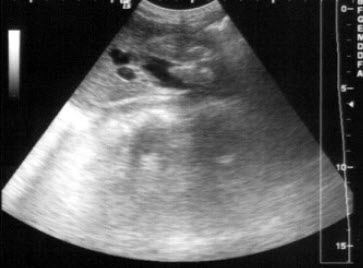

83、单项选择题

某患者因左肾区疼痛、血尿就诊,根据其超声声像图,最可能的诊断为()

A.正常图像

B.左肾结核

C.输尿管结石

D.左肾结石

E.左肾多发性结石并肾积水